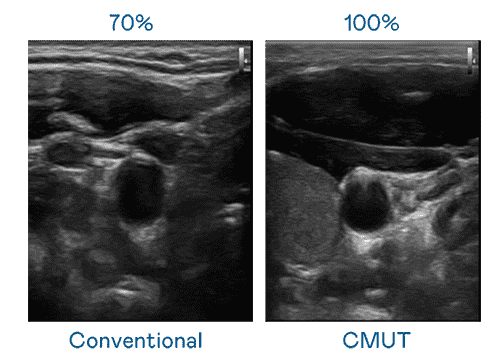

CMUT 技术是一种用电容式微机电元件来产生超音波讯号的技术。。。。与传统 PZT 压电式技术相比,,CMUT 频宽增加 30%,,更宽频的超音波讯号让影像解析度大幅提升,,,是实现高影像品质医疗超音波扫描、、、、促进精准医疗发展的关键技术。。。

大频宽带来超清晰影像

超音波影像的解析度高低,,,,首先取决于探头能发出的讯号频宽。。。。尊龙集团 CMUT 可提供高清晰的超音波讯号,,,,提供高频宽、、、高灵敏度、、、影像纹理细节更高的超音波影像,,协助医护人员缩短影像判读时间及利用精准的医疗影像进行诊断。。。。